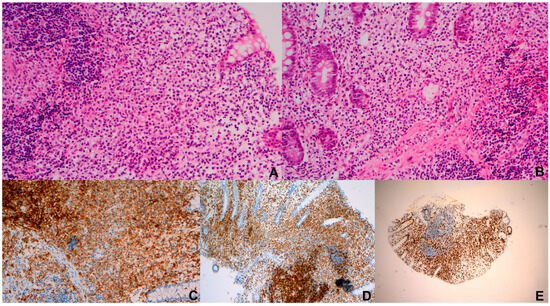

Reactive intralymphovascular immunoblastic proliferation (ILVIP) is a rare and diagnostically challenging entity that can closely mimic intravascular large B-cell lymphoma (IVLBCL). We report the comprehensive clinicopathologic features of two patients with B-cell lineage ILVIP identified in bowel resection specimens. Both patients presented with

Reactive intralymphovascular immunoblastic proliferation (ILVIP) is a rare and diagnostically challenging entity that can closely mimic intravascular large B-cell lymphoma (IVLBCL). We report the comprehensive clinicopathologic features of two patients with B-cell lineage ILVIP identified in bowel resection specimens. Both patients presented with small bowel obstruction requiring surgical intervention, and one patient was initially erroneously diagnosed with IVLBCL. Neither patient had systemic findings suggestive of lymphoma, such as lymphadenopathy, hepatosplenomegaly, or B symptoms. Histologic evaluation demonstrated focal ILVIP composed of intermediate-to-large B-lineage immunoblasts positive for CD45, CD79a, and MUM1 with polytypic light-chain expression, and negative for CD20, PAX5, CD138, Epstein–Barr virus, and HHV8. The immunoblasts showed a high proliferation index (80–100%) in both cases. Recognition of ILVIP in specimens resected for bowel obstruction in otherwise healthy patients is essential to avoid misinterpretation as intravascular lymphoma and prevent unnecessary treatment.

Figure 1